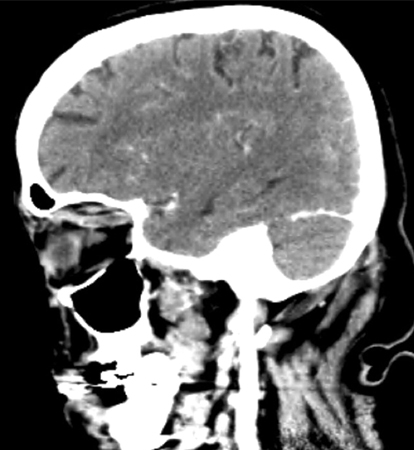

Tomografia computadorizada (TC) sagital de crânio revelando uma veia oftálmica superior direita tubular aumentada

Jones RG, Arnold B. Sudden onset proptosis secondary to cavernous sinus thrombosis from underlying mandibular dental infection. BMJ Case Rep. 2009;2009. pii: bcr03.2009.1671. Usado com permissão